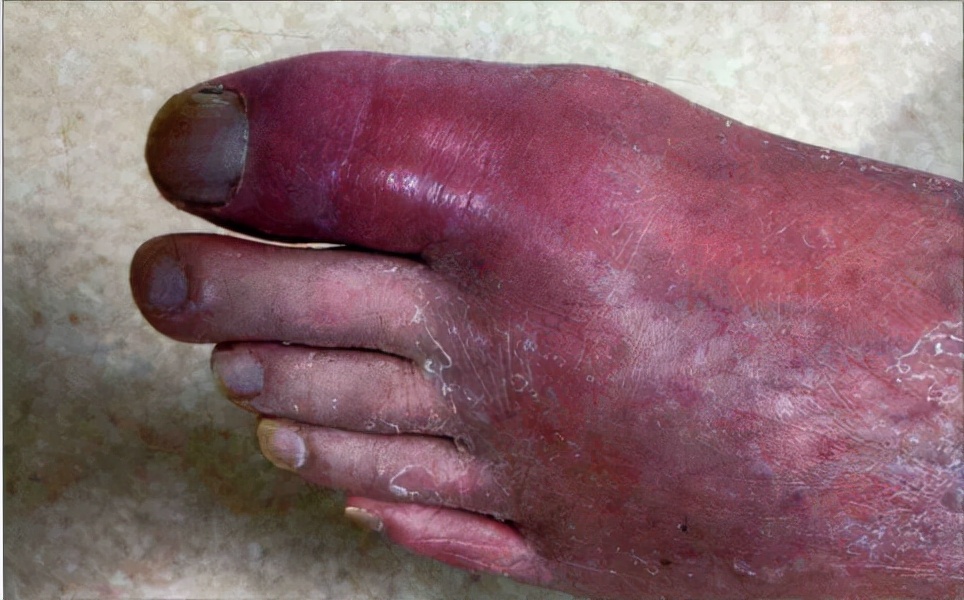

急性痛风性关节炎发作缓解后一般无明显后遗症状,有时仅有患部皮肤色素沉着、脱屑、刺痒等,称间歇期。

患部皮肤色素沉着、脱屑、刺痒

在间歇期,尿酸盐持续沉积。随着病情的进展,发作次数逐渐增多,症状持续时间延长,无症状间歇期逐渐缩短,甚至症状不能完全缓解,且受累关节逐渐增多,从下肢向上肢、从末端小关节向大关节发展,出现指、腕、肘等关节受累,少数患者可影响到肩、髋、骶髂、胸锁或脊柱关节,也可累及关节周围滑囊、肌腱、腱鞘等部位,症状和体征渐趋不典型。